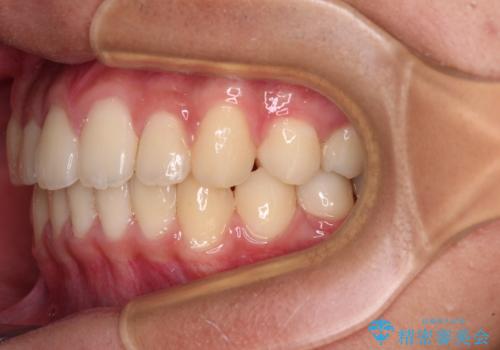

- 前歯のデコボコと隙間を気にして来院された高校生の患者様です。

下顎前歯が上顎前歯を突き上げるような咬み合わせとなっており、その影響で上顎正中に隙間ができている状態でした。

叢生の程度は軽度であり、本人もしっかりと使用する自信があるとのことだったので、インビザラインによる矯正治療を行うこととしました。

突き上げによる隙間を予防する為に、深い咬み合わせを改善するような治療計画としました。咬み合わせを改善させることはできましたが、隙間は後戻りしやすいので、通常の下顎前歯のみではなく、上顎前歯2本もワイヤーで保定を行いました。

高校生ということで、非常に短期間で治療を終えることができました。